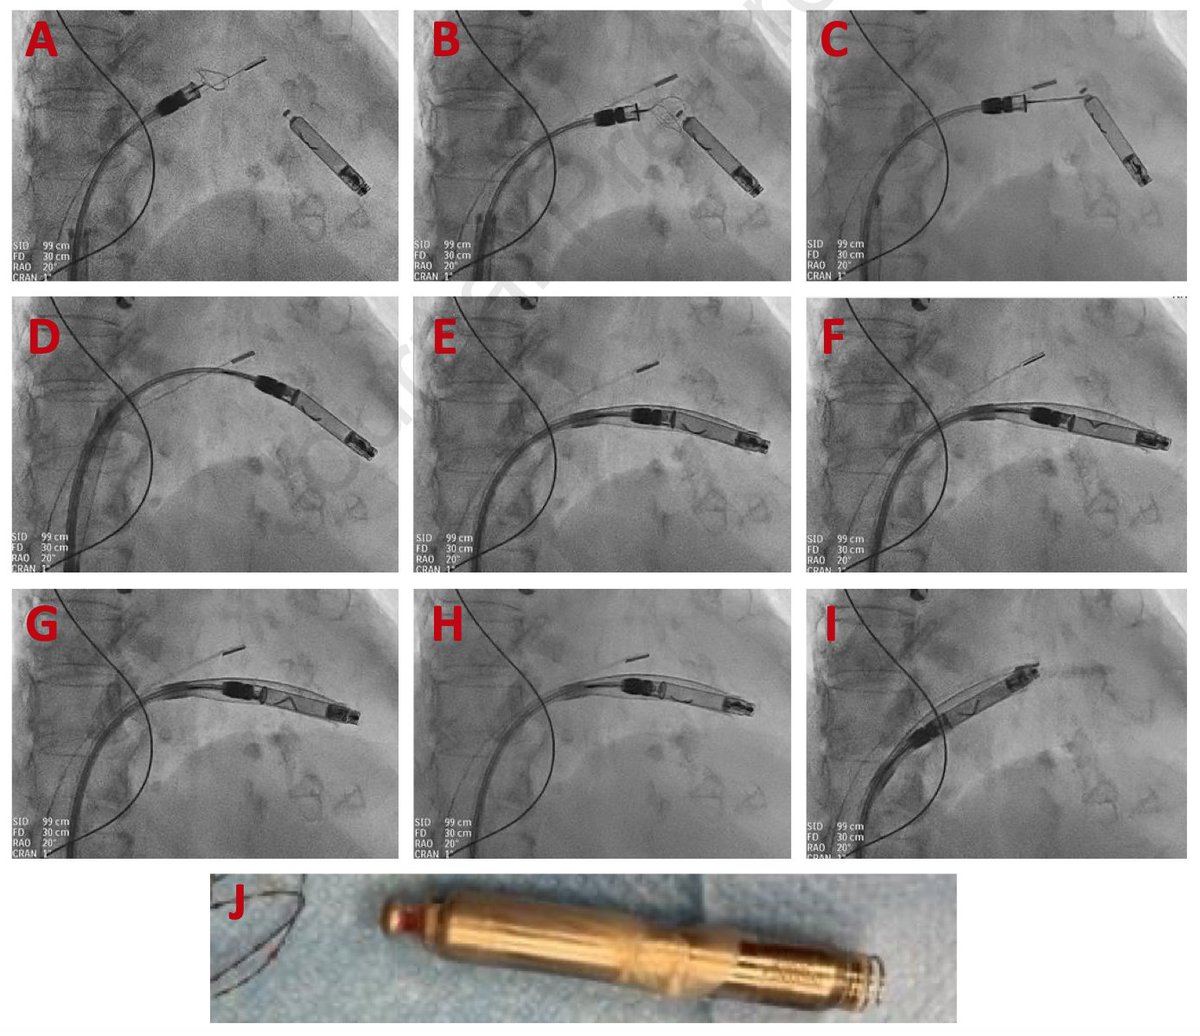

Dual Chamber Aveir from Abbott with ICE-guidance targeting the mouth of the RAA. Love it. Controlled, safe implant. Very exciting option for some patients #EPeeps

Great Aveir day at presby today including an implant on one of the smallest young patients in US to date! Looking forward to the future of pacing!